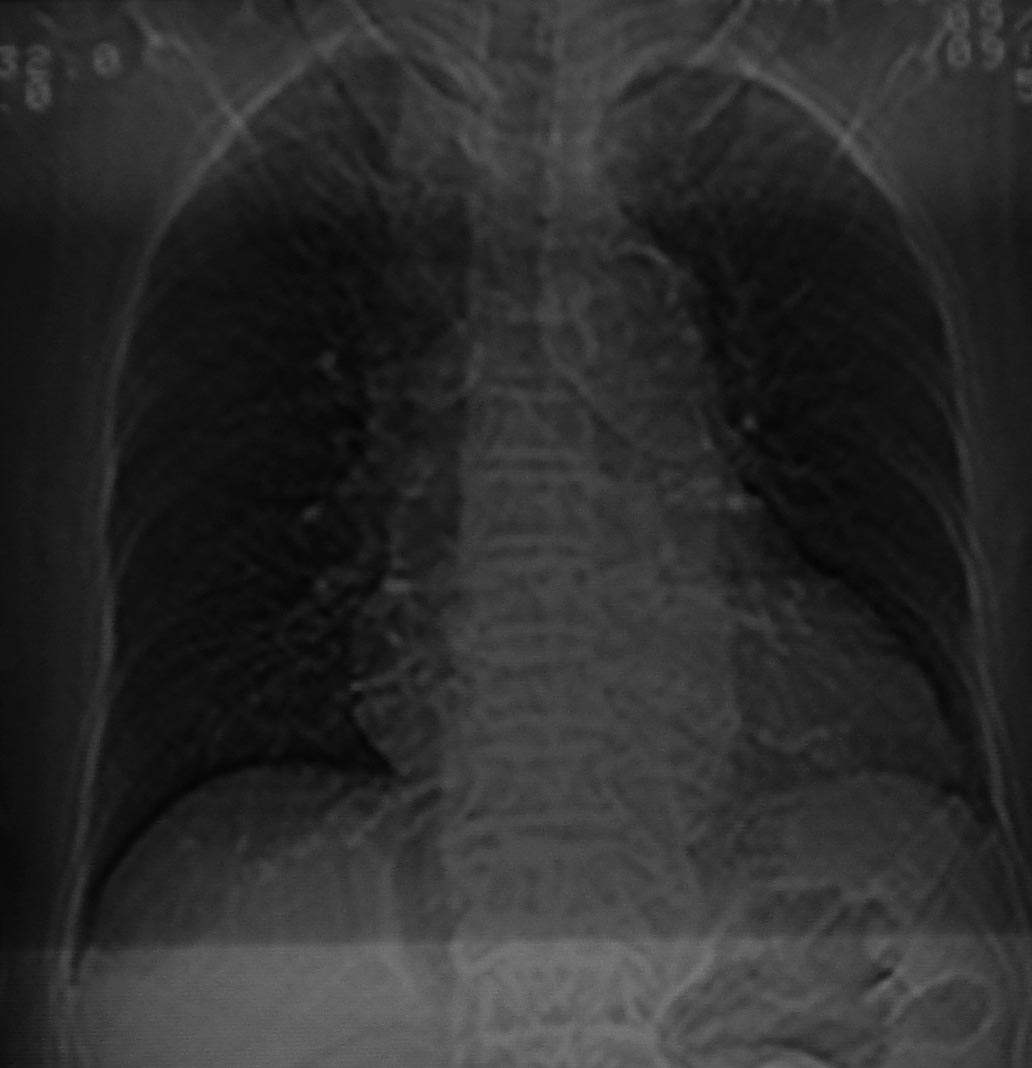

女69岁。时有咳漱、咳白色痰请老师们看看箭头所指是什么?ct值约-36.报告应该怎样写?谢谢!

说实话,图像质量一般,楼主所指为局部胸膜肥厚表现

楼主所指为局限性胸膜肥厚

局限性胸膜肥厚,心影增大,建议心超检查